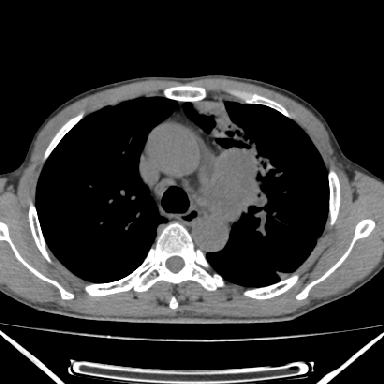

以下是引用zjzjr在2007-3-23 17:24:00的发言:[br]双侧肺门淋巴结明显肿大,以左侧为著,支气管受压变窄,肺内可见结节状及絮状高密度影,边缘模糊.考虑淋巴瘤肺内浸润.